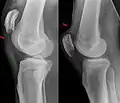

An x-ray demonstrating quadriceps tendon rupture. Note the abnormal angle of the patella and soft-tissue swelling marked by the arrow.